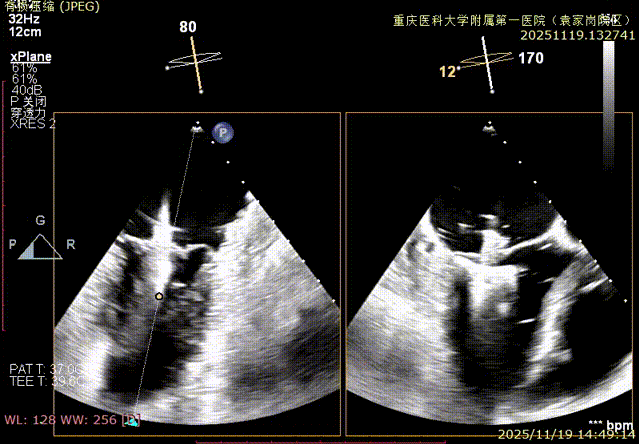

二尖瓣术前评估

复查TTE及TEE检查进一步评估二尖瓣情况。明确为FMR( Carpentier Ⅲb型),二尖瓣后叶栓系,2区瓣叶运动(视频2),重度FMR(4+), 肺静脉逆向血流;2区后叶长度1.15cm,2区前叶长度2.46cm,AP径3.2cm,瓣口面积5.1cm²,房间隔高度3.95cm,瓣叶无钙化,二尖瓣瓣膜条件适合行TEER手术。

图1、图2:2区瓣叶长度(前叶长度2.46cm,后叶长度1.15cm)及彩色血流

图3:房间隔可用高度>4cm